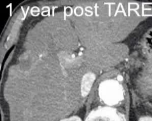

o TARE 中位治疗时间:32 天

→ 更长的治疗窗口期内,DEB-TACE 患者更容易出现非治疗区新发灶o DEB-TACE:82 天 3. 移植转化率更高

o TARE:10 人降期后移植

o DEB-TACE:4 人 六、安全性解读(容易被忽略的点)严重不良事件(≥3级)无统计学差异但死亡事件(grade 5):